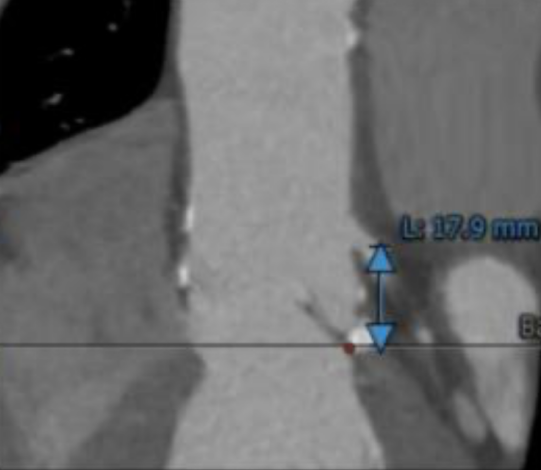

左冠开口高度17.9mm,右冠高度19.5mm,冠状动脉散在钙化。

瓣环上钙化分布及主动脉解剖